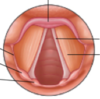

What are the vestibular and vocal folds?

Vestibular fold: superior pair; “false vocal chord”; mucosa of larynx that folds around the vestibular ligament (thickened free lower margin of quadrangular membrane)

Vocal fold: inferior pair; “true vocal chord”; mucosa of larynx that folds around the vocal ligament (thickened free upper margin of cricothyroid membrane)

Label this diagram:

What is the position of the vocal folds during forced inspiration? During phonation?

Inspiration: vocal folds abducted, rima glottides open, vestibule open

Phonation: vocal folds adducted, vestibule open

What is the shape of the vocal folds when making a low-pitched sound? High-pitched sound?

Low: short, wide